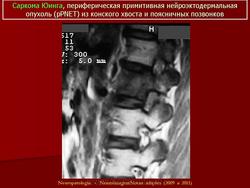

ГМ. СМ. Саркома Юинга. Периферическая примитивная нейроэктодермальная опухоль (pPNET). +

Саркома Юинга. Периферическая примитивная нейроэктодермальная опухоль (pPNET)

Примитивная нейроэктодермальная опухоль (pPNET)